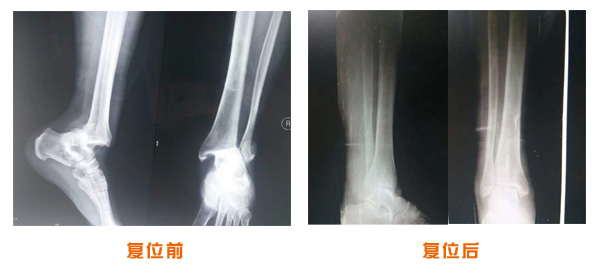

尺橈骨骨折治療前后